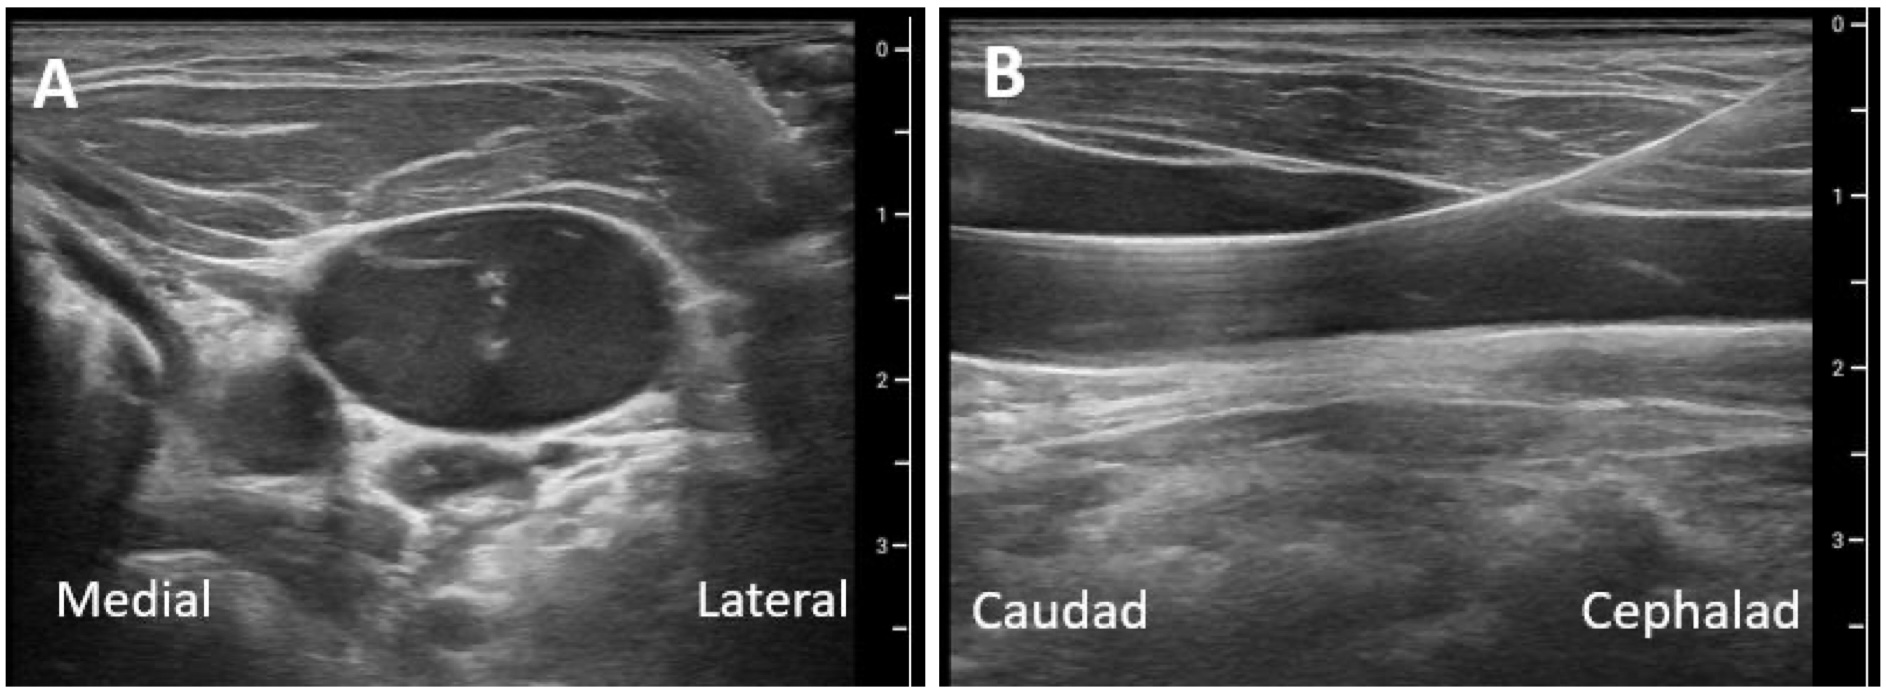

- This is followed by guidewire insertion with ultrasound confirmation (Figure 2, Video 4) and the standard Seldinger technique: make a skin nick, dilate the vessel, pass a central venous catheter over the guidewire and into the vessel with continuous guidewire control, remove the guidewire, and secure the catheter in place.

It is critically important that the guidewire is confirmed to be in the IJV and not the common carotid or subclavian artery prior to dilation and catheter insertion. Note the proximity of the subclavian artery directly below the proximal IJV, visualized near the end of Video 4, part A. Relying solely upon wire visualization (Video 5) with ultrasound before dilation can be misleading as the wire may traverse the back wall of the IJV causing the catheter to be malpositioned into the subclavian artery. Another method to avoid this complication is to confirm the wire position via manometry before vessel dilation. This requires the insertion of an angiocatheter over the wire, wire removal, and attaching a 30 cm tubing line, held vertically. If the meniscus formed by the column of blood slowly backfills the tubing, then plateaus and is non-pulsatile, this confirms venous placement, and the wire is reinserted through the angiocatheter. However, manometry may also give false reassurance in a shock state. Transesophageal echocardiography (Video 5) and/or transducing the central venous pressure with waveform confirmation are the most reliable confirmatory tests of wire location before vessel dilatation.